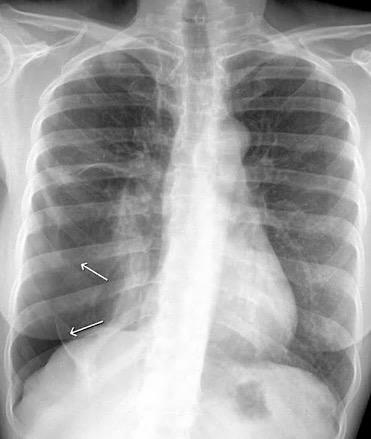

Visible en radiografías en decúbito supino de los pacientes con neumotórax por la acumulación de aire en el seno costofrénico.

“Deep sulcus sign”. Seno costofrénico aumentado en anchura y profundidad

Polireddy K et al. Blunt thoracic trauma: role of chest radiography and comparison with CT findings and literature review . Emerg Radiol 2022.

Kumaresh A et al. Back to Basics – ‘Must Know’ Classical Signs in Thoracic Radiology. Thoracic Radiology. J Clin Imaging Sci 2015.